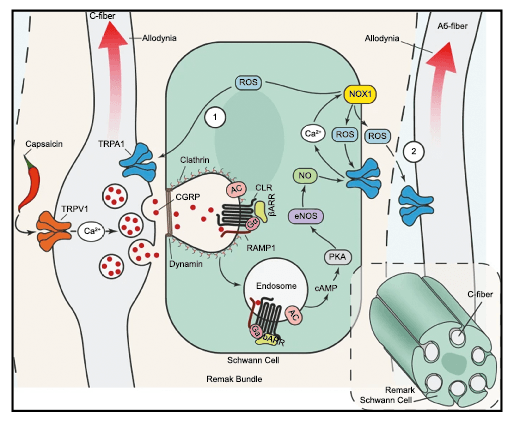

Todo lo mencionado contribuye al fenotipo del migrañoso y son vías que continuamente se están explorando para el desarrollo de nuevas terapias agudas y preventivas del dolor, más seguras y eficaces. Sin embargo, existe una controversia que gira en torno a dos cuestiones: la iniciación y el origen del dolor además de que todavía no se conoce el origen de los mecanismos neuronales que subyacen a la condición primaria en las personas susceptibles. Definitivamente la migraña implica la activación y sensibilización de las vías trigeminovasculares, así como el tronco cerebral y los núcleos diencefálicos(88). La vía aferente comienza en las aferentes vasculares nociceptivas de la duramadre que están para advertir, no para localizar. Su proyección al tálamo y la corteza y como se regula esta vía en cada nivel y por múltiples sistemas, ofrece la posibilidad de comprender los síntomas complejos y orientar las terapias. Los ataques comienzan como síntomas premonitorios, dificultad para concentrarse, bostezos, fluctuaciones del humor; y cambios homeostáticos, como la alimentación y el equilibrio de líquidos, que pueden incluir sensibilidades más generalizadas, como fotofobia y fonofobia. La fase premonitoria da paso a la fase de dolor con el sufrimiento acompañante y termina en una fase posdrómica de sentirse agotado por la experiencia. (Figura 1)

El aura de la migraña, al menos en su sentido clásico, tiene relación con la depresión cortical que se propaga por la corteza cerebral y participa como un actor paralelo cuando se producen las crisis. (Figura 2)

La importancia de la vasculatura intracraneal, o su inervación de fibras nerviosas, sigue siendo significativa. Los estudios de Ray y Wolff(94) demostraron que la estimulación de la duramadre, particularmente alrededor de los vasos sanguíneos durales y cerebrales, puede generar dolor similar al de la cefalea, además de náuseas, mientras que la estimulación lejos de los vasos fue ineficaz. Como se describió anteriormente, los vasos sanguíneos de la duramadre están ricamente inervados por axones nociceptivos no mielinizados (fibras C) y mielinizados (fibras Aδ) que se originan en el ganglio del trigémino y contienen neuropéptidos vasoactivos (serotonina, dopamina, histamina, péptido relacionado con el gel de la calcitonina). Estos datos consolidan la teoría de que la cefalea en la migraña está mediada por la activación de las fibras nerviosas nociceptivas que inervan los vasos sanguíneos meníngeos. La pregunta clave es qué hace que estas fibras se activen durante la migraña. Una propuesta en la década de 1980 fue que una “inflamación neurogénica estéril” de las meninges durales puede resultar en la activación de la inervación perivascular para desencadenar la migraña(95). La activación está impulsada por la liberación dural local de mediadores inflamatorios endógenos como CGRP, sustancia P, neuroquinina A y prostaglandinas, que aumentan el flujo sanguíneo local (predominantemente impulsado por CGRP), la fuga de proteínas plasmáticas de los vasos sanguíneos, la desgranulación de mastocitos y la agregación de las plaquetas.

Hoy en día, la migraña se describe más comúnmente como un “trastorno neurovascular” y específicamente como un trastorno del cerebro. Una teoría que ha cobrado importancia en los últimos 15 años, que sostiene este punto de vista y ha servido para explicar muchas características de la migraña que antes no se habían explorado o simplemente no estaban claras es la “sensibilización periférica y central”. La sensibilización es una característica común de muchos trastornos de dolor crónico y se supone que también está presente durante la migraña. Es una activación y sensibilización de larga duración de los nociceptores periféricos y las neuronas nociceptivas centrales y puede explicar la longevidad del ataque de migraña y la transición hacia la migraña crónica, así como síntomas relacionados específicos(96). La sensibilización central de las neuronas trigeminovasculares ha ayudado a nuestra comprensión de la base neural de la hipersensibilidad extracraneal en la migraña, la derivación del dolor y la alodinia a las áreas faciales periorbitarias y cutáneas(97). Es probable que la sensibilización de las neuronas trigeminotalámicas explique la alodinia cutánea generalizada en las regiones extracefálicas(98).

Un principio importante de esta teoría es que el desencadenante principal de la migraña proviene de la periferia, en los vasos sanguíneos de la duramadre, con la activación del sistema trigeminovascular proveniente del disparo de las neuronas trigeminales periféricas de primer orden en respuesta a una lesión nociceptiva o señales provenientes de las meninges que liberan mediadores neuroinflamatorios. La activación sostenida de las neuronas nociceptivas meníngeas durales provoca la activación secuencial y la sensibilización de las neuronas trigeminovasculares de primer orden (nociceptores periféricos), segundo orden (a nivel del TCC-complejo trigémino cervical) y tercer orden (trigeminotalámico), (Figura 5) así como la activación ascendente del cerebro, tallo y otras estructuras diencefálicas(97).

Los terminales axónicos de las fibras nerviosas nociceptivas que inervan la duramadre contienen neuropéptidos vasoactivos CGRP, sustancia P, neurocinina A y péptido activador de la adenilato ciclasa pituitaria (PACAP)(25) (Figuras 13 y 14), que se cree que son liberados tras la estimulación que causa la vasodilatación de los vasos durales y piales(26) (Figura 15).

La activación del sistema trigeminovascular da como resultado la liberación de varios neuropéptidos basados en las inervaciones simpática, parasimpática y sensorial de la vasculatura craneal, que se resumen en la figura 23.

La inervación simpática se caracteriza por NPY y norepinefrina(52), ambos de los cuales son vasoconstrictores, mientras que las fibras parasimpáticas se caracterizan por VIP y PACAP, que se encuentran entre los vasodilatadores más potentes(24).

Las inervaciones sensoriales se caracterizan por la sustancia P, CGRP y PACAP (53).